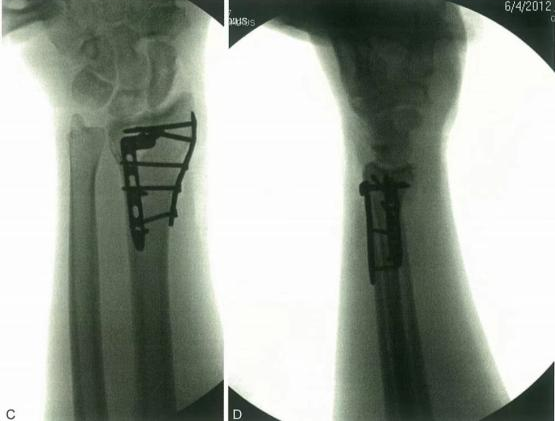

Внешние фиксационные скобки полезны для начальной или дополнительной обработки при определенных переломах дистального радиуса.

Внешний фиксатор нейтрализует осевые напряжения, действующие на дистальный радиус во время сокращения групп мышц предплечья. Фиксация может быть или не быть через запястье, или может быть добавлена дополнительная фиксация.

Параллельная тяга не полностью восстанавливает наклон пальма, но нейтральное положение приемлемо. После операции запястье закрепляется в трубчатом литье в вращающемся заднем положении в течение 10 дней, пока боль и отек не исчезнут.